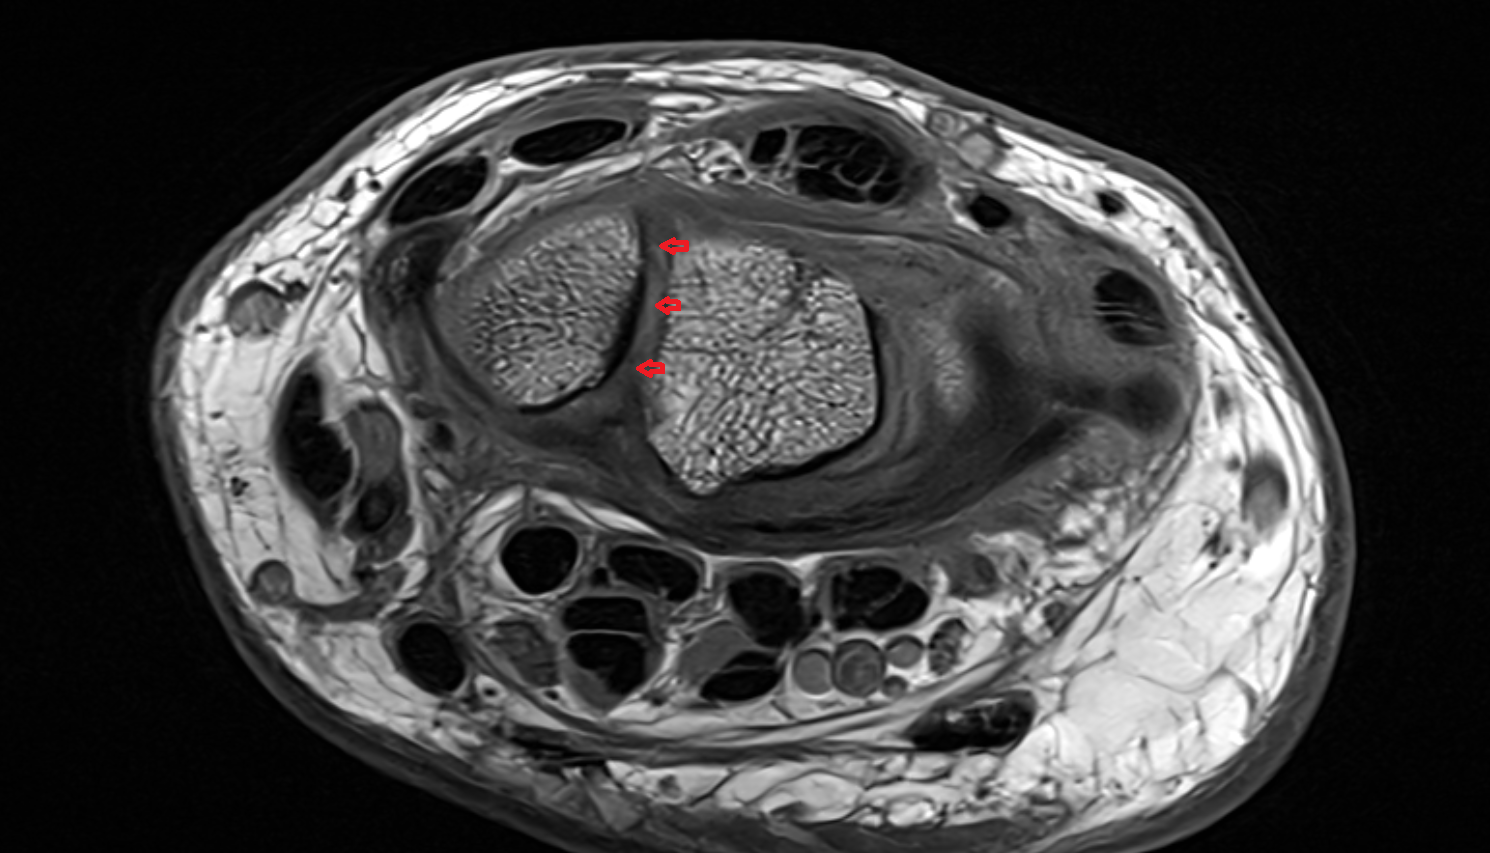

- Anterior cruciate ligament

- Posterior cruciate ligament

- Knee Joint